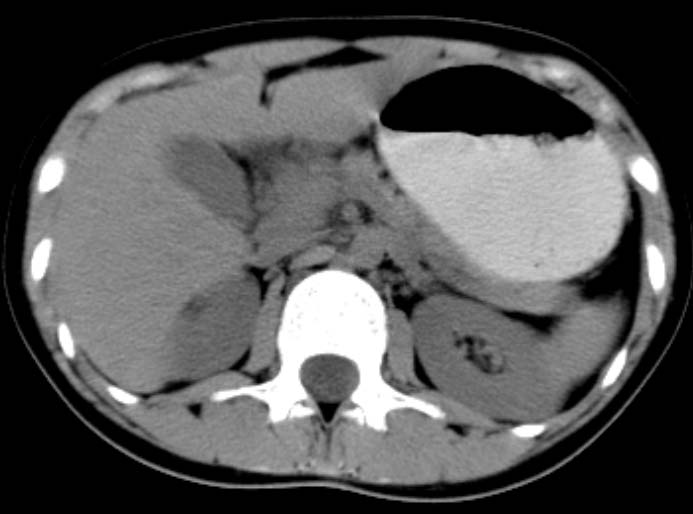

女,14岁。腹痛3天。腹部触诊未触及包块。碘剂阳性未增强。求助战友。。。。。。。。。。。

胰头部明显肿大,胰周间隙浸润,考虑胰腺炎可能性大

胰头部增大,周围模糊,有渗出,胰腺炎可能性大,建议结合化验检查;左侧输尿管上段略扩张.

胰头部明显肿大,胰头周脂肪密度加大。十二指肠环扩大受压。胰管未见确切扩张。考虑胰腺炎可能性大。建议增强扫描。

胰头部增大,周围结构模糊,并明显见渗出。支持:急性胰腺炎!

1)急性胰腺炎。2)肝右叶后上段肝内胆管结石。3)左侧输尿管上段扩张,原因待查。